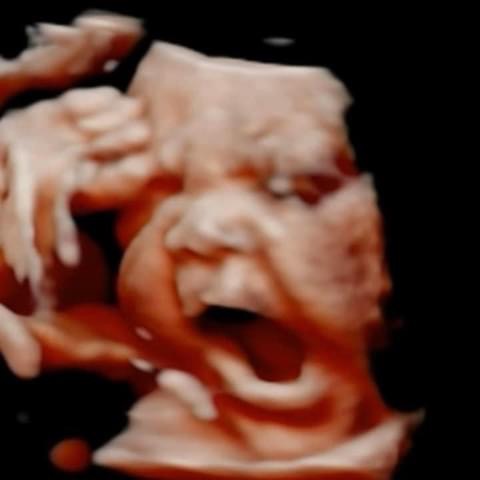

All photos are from our equipment and are of our actual clients.